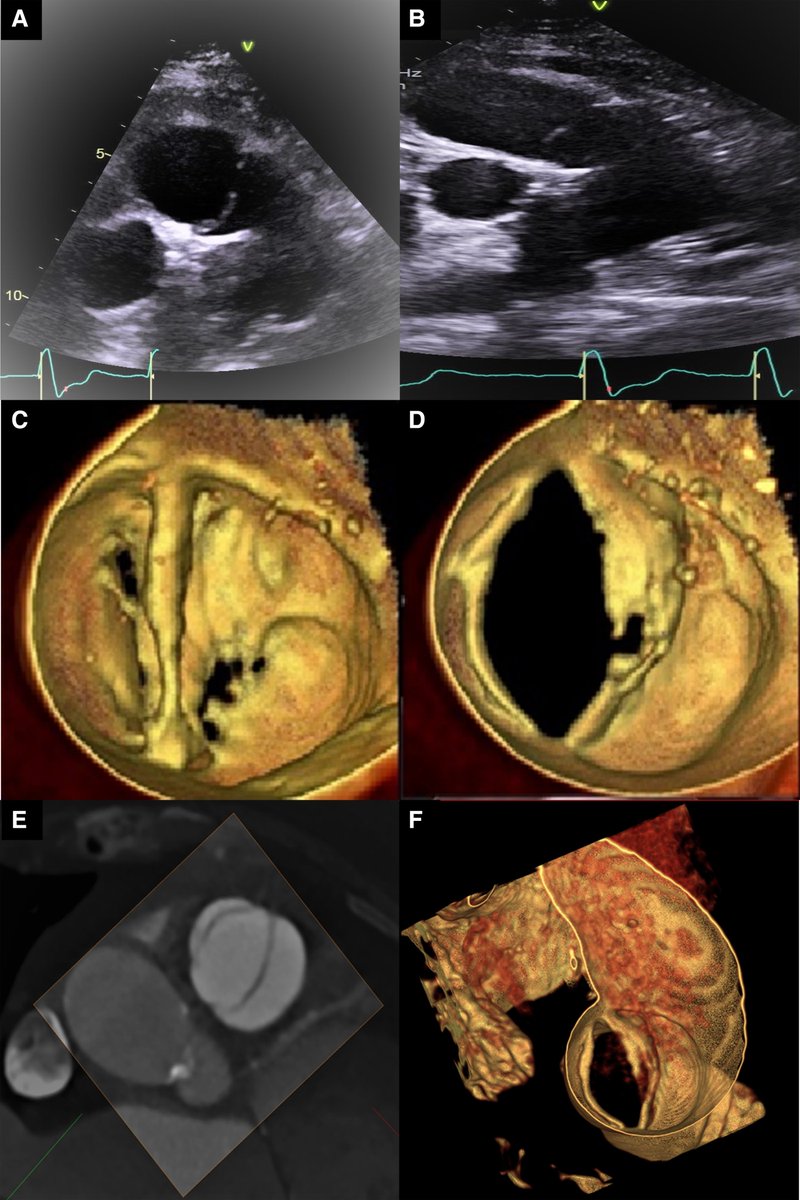

33y/o male, non-Hodkin's lymphoma, blood eosinophils 46%, stroke. TTE apical LV obliteration ("compact gelatinous mass"). Dx: endomyocardial fibrosis associated with hypereosinophilic syndrome. CMR LV apical obliteration and LGE double V sign.

🌟Mitral subvalvar involvement in rheumatic MS 👀TEE shows that obstruction may occur in 2 levels: 🌟valvular level (comissural fusion) 🌟subvalvular level (chordal fusion / thickening) 🚨A predictor of worse results in balloon MV valvuloplasty and ⬆️risk of complications